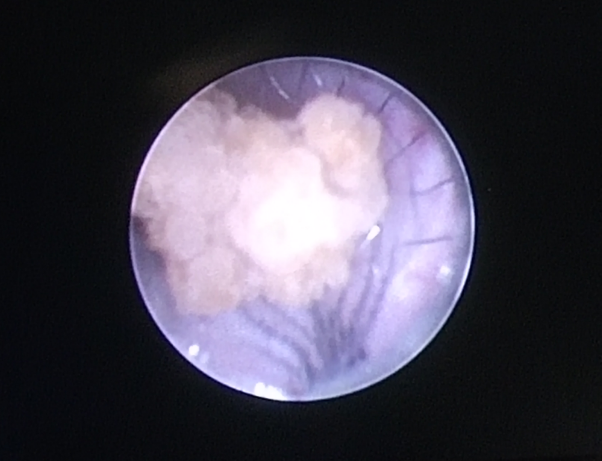

如果结石大于5mm,可以选择体外碎石,也可选择输尿管镜取石。

一般来说,输尿管上段的结石,体外碎石效果较好;输尿管中下段的结石,输尿管镜取石的把握度较大。

4.输尿管镜手术:对于较大的结石或无法通过药物和自然排出的结石,可以考虑采用输尿管镜手术。该手术通过输尿管插入镜子,将结石碾碎或取出,通常不需要开腹手术。